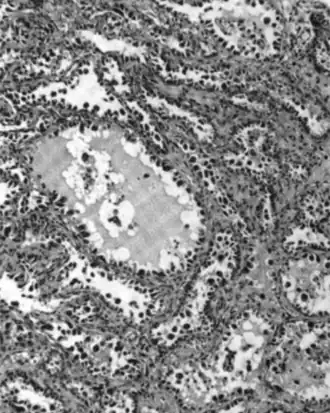

Mucinous adenocarcinoma

Mucinous adenocarcinomas make up 5–10% of epithelial ovarian cancers. Histologically, they are similar to intestinal or cervical adenocarcinomas and are often actually metastases of appendiceal or colon cancers. Advanced mucinous adenocarcinomas have a poor prognosis, generally worse than serous tumors, and are often resistant to platinum chemotherapy, though they are rare.[29]